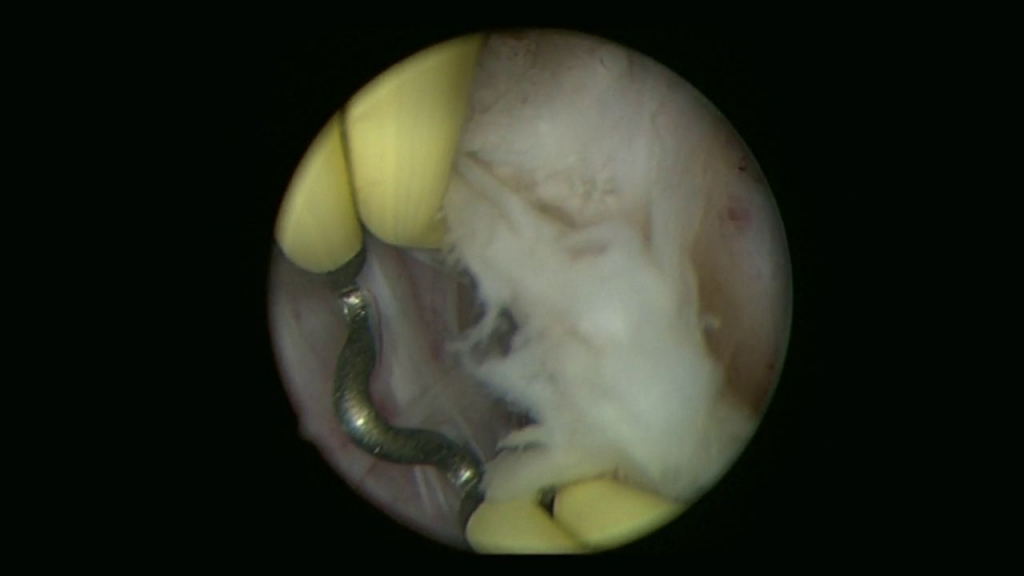

Мартов А.Г. - Биполярная трансуретральная электроэнуклеация простаты